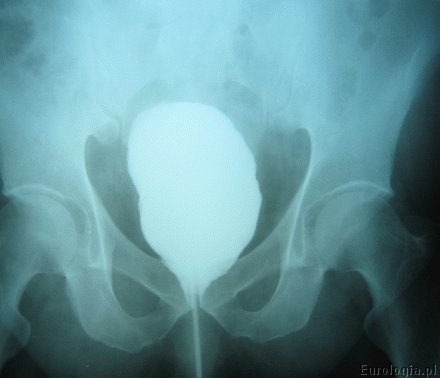

Cystografia

Cystografia - badanie radiologiczne polegające na wypełnieniu pęcherza środkiem kontrastującym i wykonaniu zdjęcia RTG. Pacjent układany jest na stole rentgenowskim na plecach. Następnie zakładany jest cewnik do pęcherza moczowego, przez który podawany jest rozcieńczony środek kontrastujący np. Uropolina. Standardowo podaje się około 250 - 300 ml kontrastu. Po wypełnieniu pęcherza wykonywane jest zdjęcie rentgenowskie, które pozwala na ocenę pęcherza moczowego.

Fot. Cystografia - obraz prawidłowy